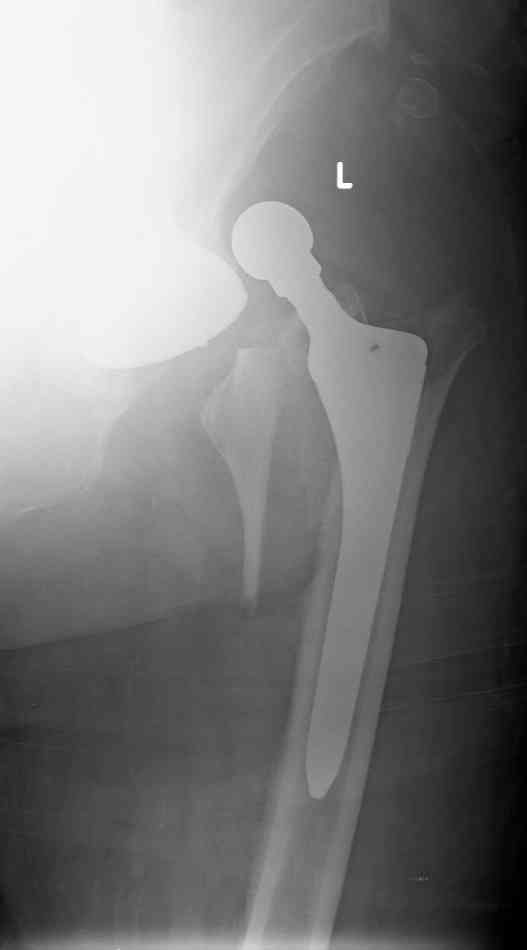

Periprosthetic fx dislocation after THR

Patient 77 yaers old man falled two day after elective THR operation.

Was done noncemented THR,Direct Lateral Approuch .During posedure wasn't any complication.Now we have Vancouver AL fracture (to be more prosize between A to B1).What your sudgests?

Good evening!In the morning operation was done.

Socket is acceptable position so wasn't change.Fracture proximal femur - three part I mean G.T & L.T. After removal femoral prosthesis was done reduction of L.T & Calca. Reaming and insert new prosthesis with distal locking by 3 screws,reduction G.T.and fixation by 4 cyrclages.

Connection head and reduction femur.In the end surgery got stable joint.

Here x-ray after operation.